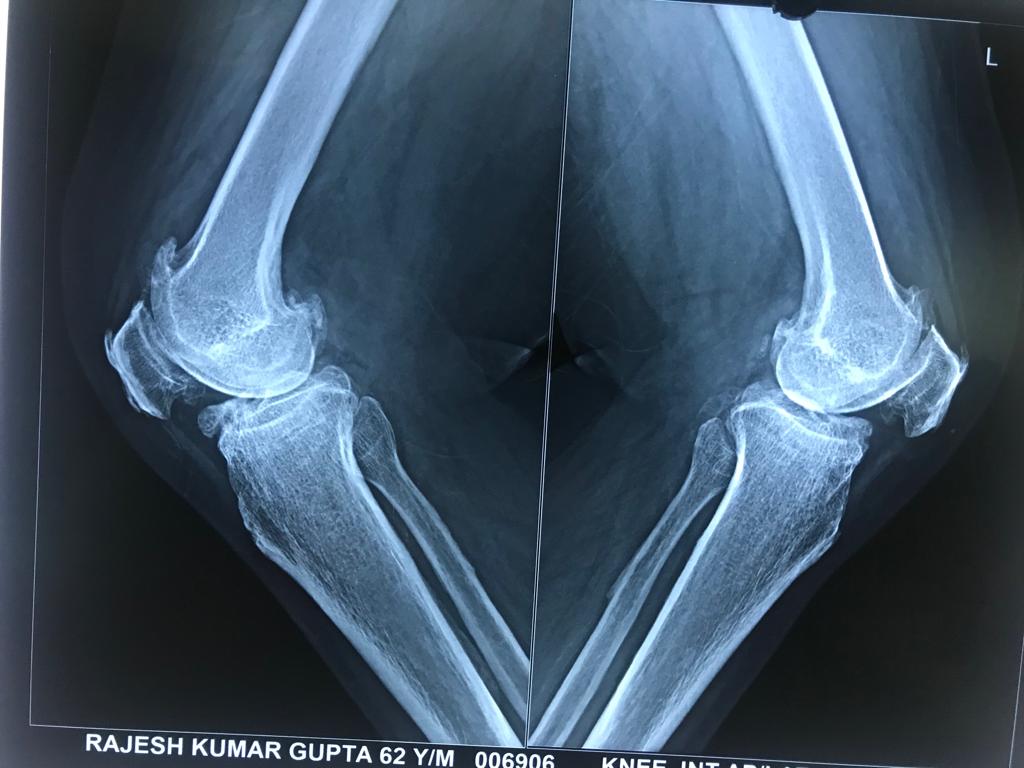

Case I: This is a case of bilateral total knee replacement